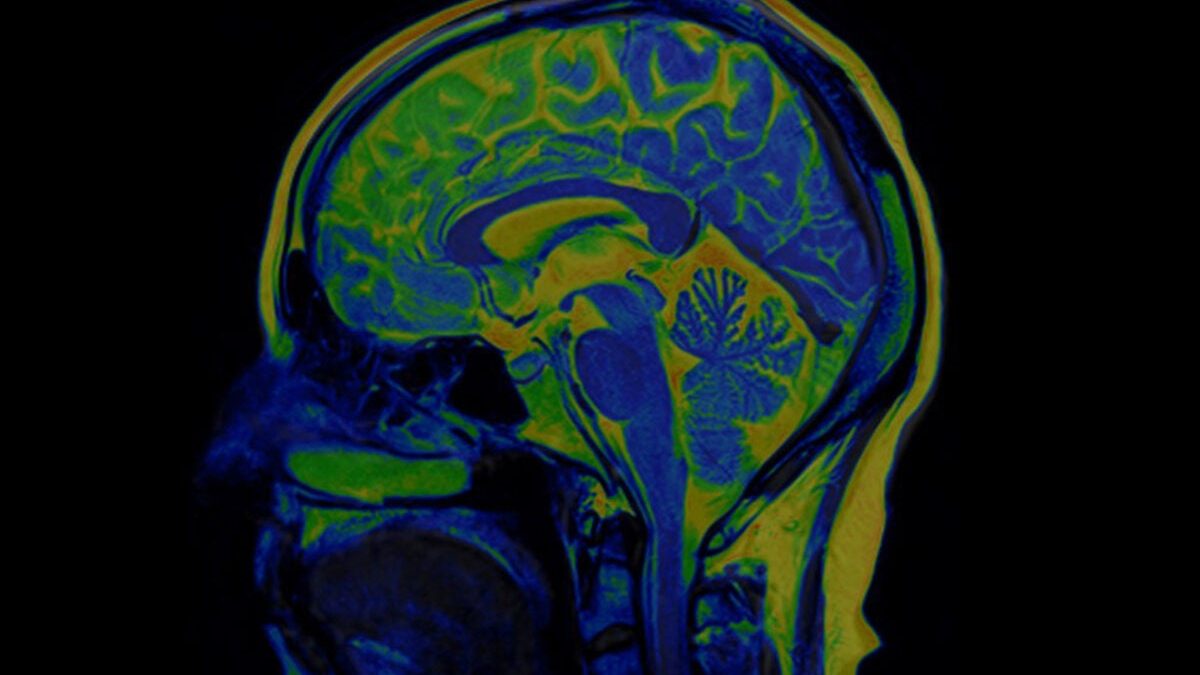

One of the first spectroscopic imaging-based studies of neurological injury in COVID-19 patients has been reported by researchers at Harvard-affiliated Massachusetts General Hospital (MGH) in the American Journal of Neuroradiology. Looking at six patients using a specialized magnetic resonance (MR) technique, they found that COVID-19 patients with neurological symptoms show some of the same metabolic disturbances in the brain as patients who have suffered oxygen deprivation (hypoxia) from other causes, but there are also notable differences.

The researchers used 3 Tesla Magnetic Resonance Spectroscopy (MRS), a specialized type of scanning that is sometimes called a virtual biopsy. MRS can identify neurochemical abnormalities even when structural imaging findings are normal. COVID-19 patients’ brains showed N-acetyl-aspartate (NAA) reduction, choline elevation, and myo-inositol elevation, similar to what is seen with these metabolites in other patients with white matter abnormalities (leukoencephalopathy) after hypoxia without COVID. One of the patients with COVID-19 who showed the most severe white matter damage (necrosis and cavitation) had particularly pronounced lactate elevation on MRS, which is another sign of brain damage from oxygen deprivation.

Compared to conventional structural MR imaging, “MRS can better characterize pathological processes, such as neuronal injury, inflammation, demyelination, and hypoxia,” adds Weerasekera. “Based on these findings, we believe it could be used as a disease and therapy monitoring tool.”